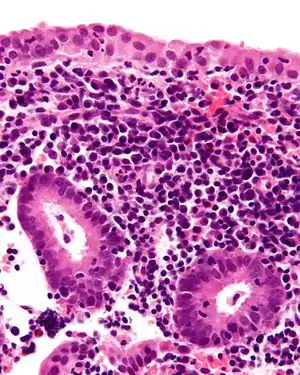

![]() На мікрографії хронічний ендометрит. Чітко видно лімфоцитарні плазмоцити та нейтрофіли. На мікрографії хронічний ендометрит. Чітко видно лімфоцитарні плазмоцити та нейтрофіли. | |

Хронічний ендометрит характеризується наявністю плазматичних клітин у стромі. Може бути видно лімфоцити, еозинофіли і навіть лімфоїдні фолікули, але за відсутності саме плазматичних клітин цього недостатньо для підтвердження гістологічного діагнозу. Оскільки схожа картина може бути виявлена у приблизно 10% усіх біопсій ендометрію, проведених із-за нерегулярних кровотеч. Найпоширенішими організмами є Chlamydia trachomatis ( хламідія ), Neisseria gonorrhoeae (гонорея), Streptococcus agalactiae (група B Streptococcus), Mycoplasma hominis, туберкульоз та різні віруси. Більшість з них здатні викликати хронічні запальні захворювання органів малого тазу. Пацієнти, які страждають на хронічний ендометрит, також можуть мати рак шийки матки або ендометрію (хоча інфекції є більш поширеною причиною). Терапія антибіотиками в більшості випадків є лікувальною (залежить від причини виникнення), з досить швидким купіруванням симптомів за 2–3 дні. Жінки з хронічним ендометритом також мають високий ризик втрати вагітності, проте лікування поліпшує ситуацію. [18] [19]